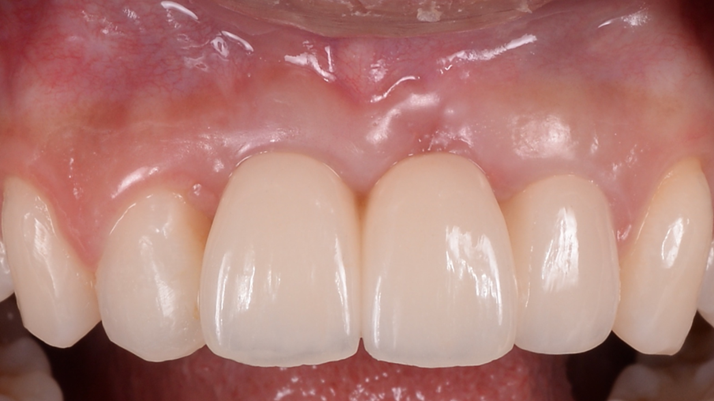

“AnyRidge is perfect for the anterior esthetic zone due to its strong initial stability & fast osseointegration.

Plus, KnifeThread® ensures space maintenance when using the PET/Socket Shield/Root Membrane Technique, showing excellent bone growth.”